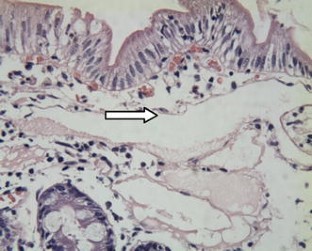

Fig. 1

Fig. 2